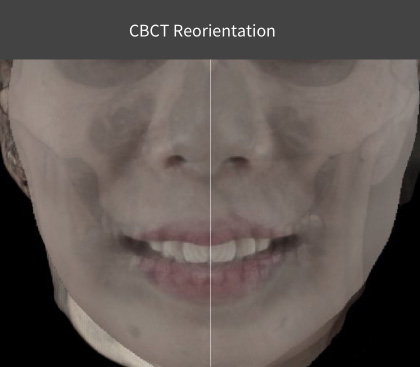

- CBCT reorientation

- Natural head position

- 3D facial matching

CBCT Reorientation

- Successful surgery requires accurate preoperative diagnosis & precise surgical planning

- CBCT analysis errors caused by slight patient movement can have significant impact on final surgical outcome

- Reorientation function corrects any patient position error during CBCT scan to provide best data for precise diagnosis